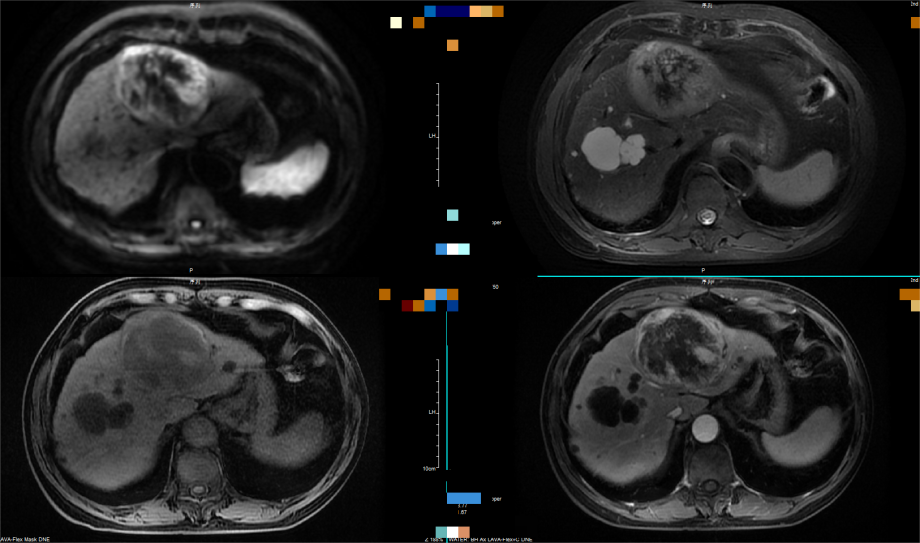

(图4)肝脏增强MRI提示:左肝巨块型病灶,弥散受限,T2WI混杂高信号,增强“快进快出”,诊断为肝癌。